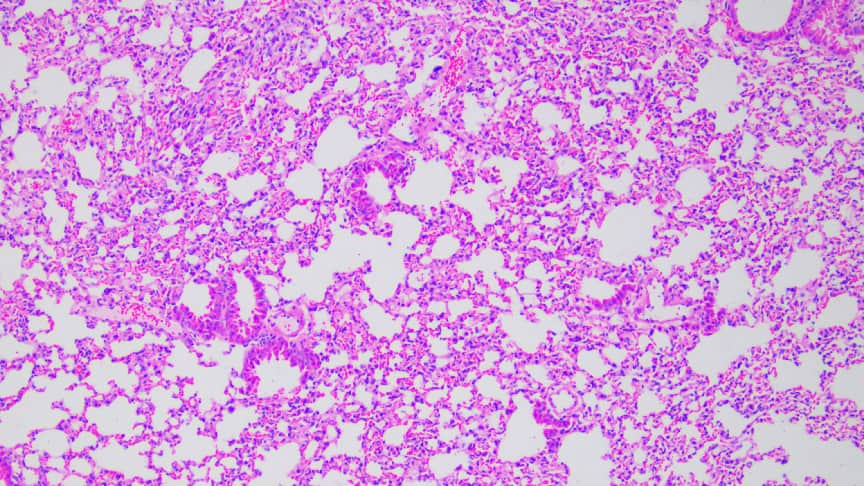

HE染色

简称HE染色法 ,石蜡切片技术里常用的染色法之一 。染液为碱性 ,主要使细胞核内的染色质与胞质内的核糖体着紫蓝色 ;伊红为酸性染料 ,主要使细胞质和细胞外基质中的成分着红色 。HE染色法是组织学、胚胎学、病理学教学与科研中最基本、使用最广泛的技术方法。

结果判读:细胞核被染成深蓝黑色;细胞浆被染成粉红色;软骨及钙盐被染成蓝色;胶原纤维染成淡粉红色,嗜酸性细胞及嗜酸性颗粒呈鲜红色;弹力纤维呈淡粉红色;某些蛋白性物呈粉红色等。